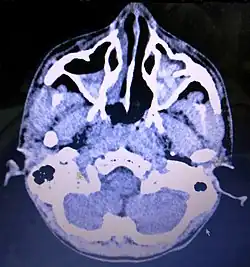

Maxillary sinus cancer that has spread to the brain -